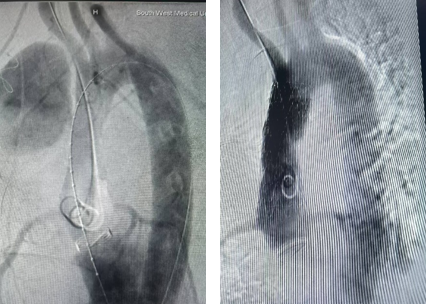

第二次手术正式开始。麻醉科全麻显效后,手术分为两个部分,首先实施临时心脏起搏器安置术,再实施主动脉造影+胸主动脉假性动脉瘤覆膜支架隔绝术。

心内科唐志豪医师熟练地穿刺、置入静脉鞘管、放置临时起搏电极、调整临时起搏器电极位置并固定,以120次/分起搏……血压下降理想,方便升主动脉支架释放。

斯光晏教授、胡伟博士、袁罡博士、徐燕能博士从右侧股动脉入路,经鞘送入戈尔40-100mm覆膜支架至升主动脉,精确定位后,缓慢释放支架主体……

缓慢撤出支架输送系统后,造影见主体支架位置固定、展开良好,血流较术前缓慢。随后经胸超声引导下,向瘤腔注射凝血酶,见瘤腔内完全血栓化,血流信号明显减少,置入引流管,见少量淡血性液体流出,假性动脉瘤消失。历时2小时,手术顺利